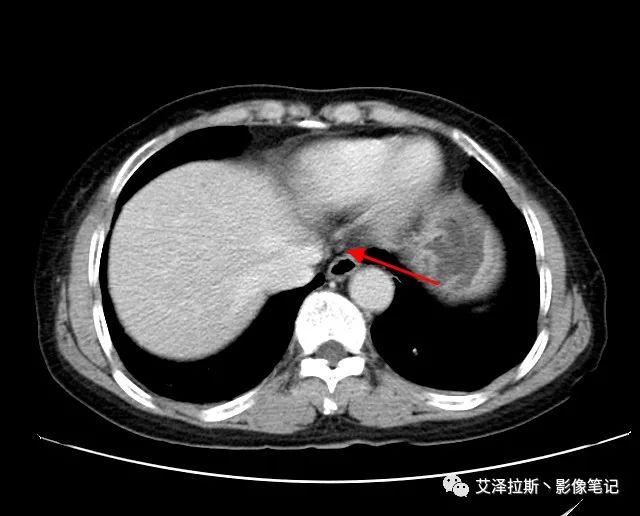

圖1 平掃+增強(qiáng)各期

【影像所見】 胃竇部狹窄,胃壁環(huán)形增厚,小彎側(cè)見一巨大潰瘍,周圍伴“環(huán)堤征”,漿膜面不完整,胃周脂肪見網(wǎng)格狀條索影,病灶與肝臟左葉、胰腺鉤突脂肪間隙消失,增強(qiáng)掃描病灶明顯強(qiáng)化。引流區(qū)內(nèi)約15個區(qū)域淋巴結(jié)受累。

【診斷意見】 胃竇部胃癌(T4N3期) 該病例腫塊突破漿膜層,與肝臟左葉、胰腺鉤突分界不清,脂肪界面消失,定為T4期; 受累及的淋巴結(jié)為15個區(qū)域,定為N3; 有無遠(yuǎn)處轉(zhuǎn)移尚不明確,所以M期暫時無法確定。